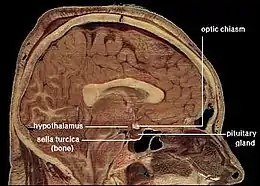

Located at the base of the brain, the pituitary gland is protected by a bony structure called the sella turcica of the sphenoid bone. | |

Structure

In humans, the pituitary gland rests upon the hypophyseal fossa of the sphenoid bone, in the center of the middle cranial fossa. It sits in a protective bony enclosure called the sella turcica, covered by the dural fold diaphragma sellae.[3]

Location of the pituitary gland in the human brain

Location of the pituitary gland in the human brain Pituitary and pineal glands